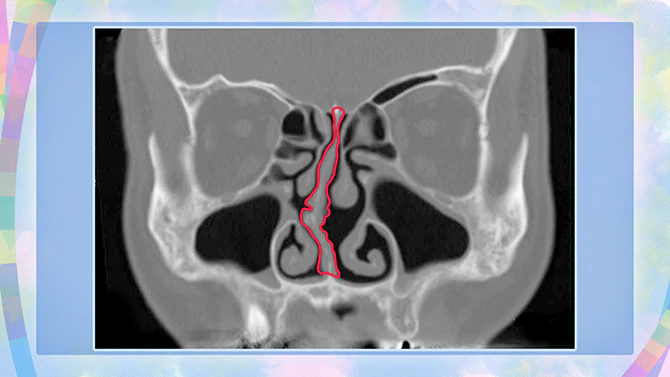

비중격(비추카쿠)이 현저하게 구부러져 있는 사람

좌우의 비강을 분리하고 있는 벽 「코 중격」은, 다소 구부러져 있는 것도 드물지 않지만, 현저하게 구부러져 있으면, 코 막힘이 일어나기 쉬워져, 만성 부비강염을 발병하기 쉬워집니다.